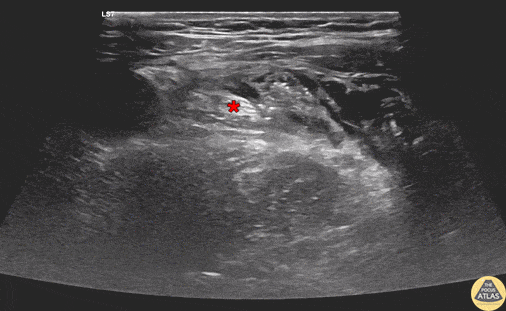

Demonstration of an in-plane femoral nerve block, with needle seen entering from lateral to medial, depositing anesthetic in the space just lateral to the femoral nerve (*). This block was performed in a 50s year-old male patient with an intertrochanteric femur fracture, with successful analgesia until surgery was performed the next day. Drs. Kathleen Joseph, PGY-2 and Reid Haflich, PGY-4 Denver Health Residency in Emergency Medicine